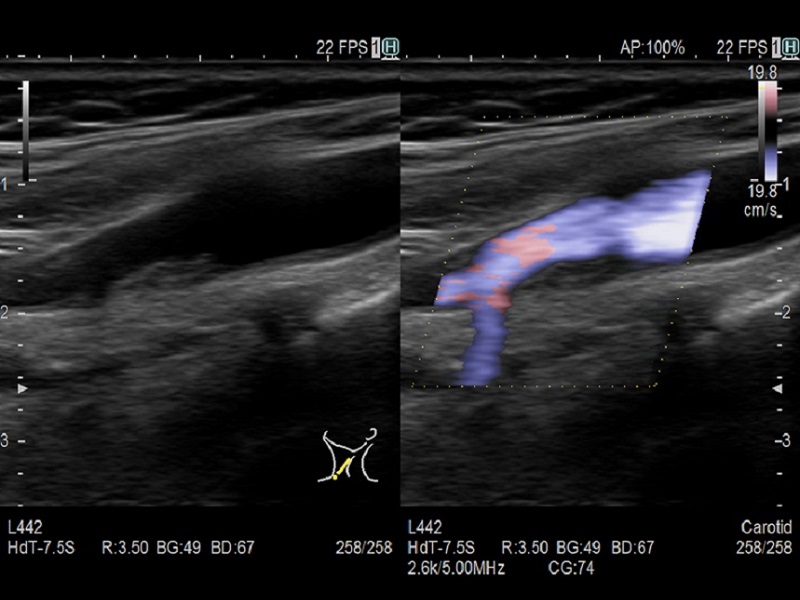

- Colored: Color Flow Mode, eFLOW

Dormed Hellas AR65 – Vascula Carotid Dop Dormed Hellas AR65 – Vascular Carotid Dual CF